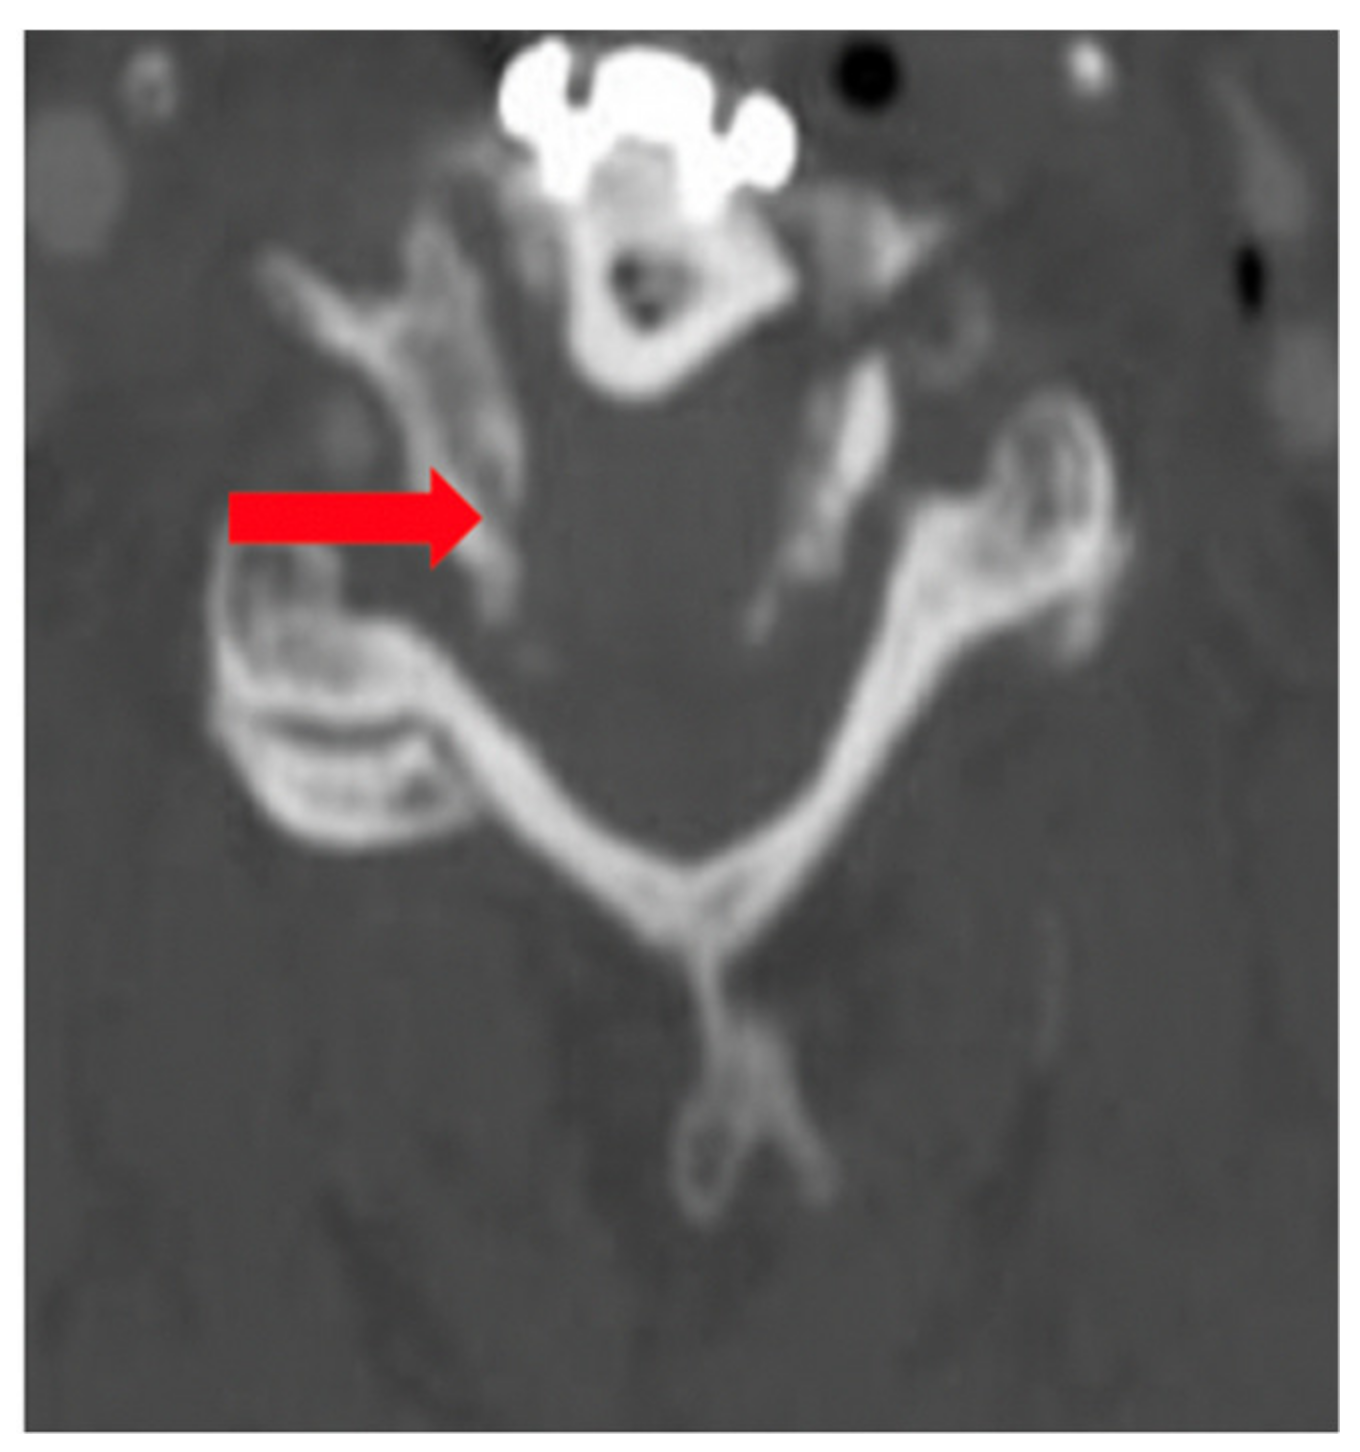

The patient was asymptomatic immediately post-op. Computed tomography (CT) angiography showed anterolateral bony defect at C5 (Figure 2). The study also revealed 50% focal narrowing of the left VA at C5; consistent with focal thrombus versus external compression possibly due to bone wax (Figure 3). The study confirmed acceptable cervical alignment, operative decompression, and hardware placement.

Figure 2. Computed tomography (CT) Scan (arrow denoting bony defect C5).